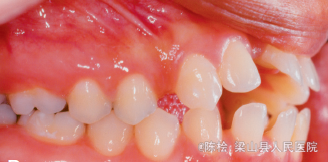

18岁女性,主诉前牙咬不到

伸舌吞咽习惯,前牙4-4开合3mm,上下牙列散隙

诊断:开合 治疗:双侧第一第二磨牙带环上制作TPA,同时弓丝伸至前牙段弯成腭刺,腭刺破除伸舌吞咽的不良习惯,TPA压低双侧后牙,降低后牙槽高度,改善开合.